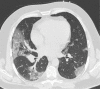

Chest CT has a potential role in the diagnosis, detection of complications, and prognostication of coronavirus disease 2019 (COVID-19). Implementation of appropriate precautionary safety measures, chest CT protocol optimization, and a standardized reporting system based on the pulmonary findings in this disease will enhance the clinical utility of chest CT. However, chest CT examinations may lead to both false-negative and false-positive results. Furthermore, the added value of chest CT in diagnostic decision making is dependent on several dynamic variables, most notably available resources (real-time reverse transcription-polymerase chain reaction [RT-PCR] tests, personal protective equipment, CT scanners, hospital and radiology personnel availability, and isolation room capacity) and the prevalence of both COVID-19 and other diseases with overlapping manifestations at chest CT. Chest CT is valuable to detect both alternative diagnoses and complications of COVID-19 (acute respiratory distress syndrome, pulmonary embolism, and heart failure), while its role for prognostication requires further investigation. The authors describe imaging and managing care of patients with COVID-19, with topics including (a) chest CT protocol, (b) chest CT findings of COVID-19 and its complications, (c) the diagnostic accuracy of chest CT and its role in diagnostic decision making and prognostication, and (d) reporting and communicating chest CT findings. The authors also review other specific topics, including the pathophysiology and clinical manifestations of COVID-19, the World Health Organization case definition, the value of performing RT-PCR tests, and the radiology department and personnel impact related to performing chest CT in COVID-19. ©RSNA, 2020.